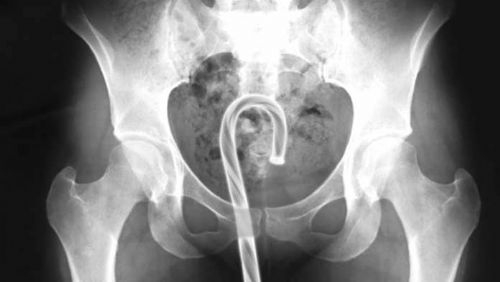

O ŞİŞE ORAYA BAKIN NASIL GİRMİŞ

Röntgen filmlerinden çıkan akıl almaz şeyler

Hastane koridorlarına düşenler bilir… Doktora görün, tahlilleri yaptır, röntgenleri çektir falan filan derken insanın ömründen ömür gider. Gelin görün ki bu sefer çektirilen röntgenlerde öyle ilginç şeyler çıkmış ki ağzımız açık kaldı…